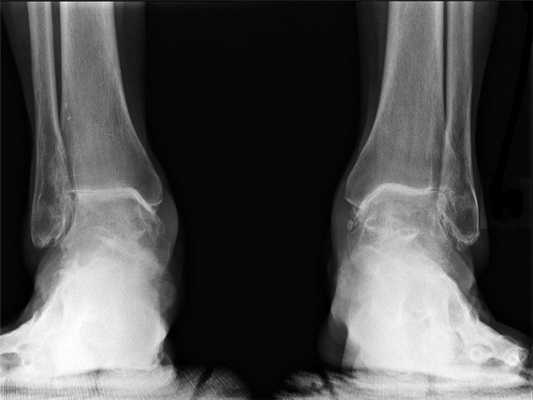

Первым методом, к которому прибегает врач, является рентген как самый недорогой и достаточно информативный метод визуализации. На снимках можно будет определить перелом, вывих, большие трещины, объемные образования в области сустава.